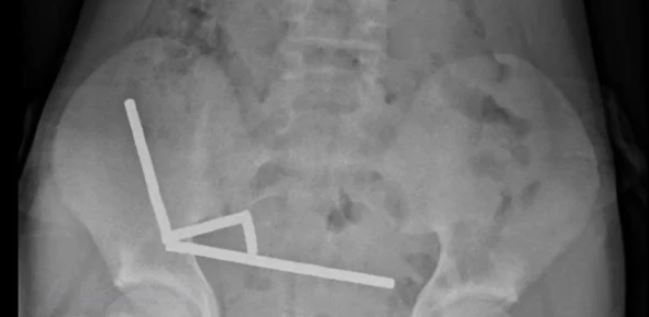

نیوزی لینڈ میں ایک 13 سالہ لڑکا تقریباً 80 سے 100 انتہائی طاقتور نیوڈیَمِیم (neodymium) مقناطیسی گولیوں کو نگل گیا۔ یہ گولیاں ایک آن لائن مارکیٹ پلیس (رپورٹ کے مطابق Temu) سے خریدی گئی تھیں۔ بچے کو چار دن تک معدے / پیٹ میں درد رہا، پھر اسپتال لایا گیا جہاں ایکس رے سے مقناطیسوں کی زنجیری شکلوں کا مشاہدہ ہوا جنہوں نے مختلف حصوں میں جمع ہو کر نقصان پہنچایا ہوا تھا۔ لڑکے کی سرجری کی گئی اور مقناطیسوں کے ساتھ ساتھ آنتوں کے اس حصے کو نکالنا پڑا جہاں ٹشوز شدید نقصان کا شکار ہوئے تھے۔ طبی ماہرین نے اس واقعے کو “بچوں کے لیے انتہائی خطرناک” اور بالخصوص آن لائن دستیابی کی وجہ سے ’لازمی روکا جانے والا اقدام‘ قرار دیا ہے۔ واضح رہے کہ جب بچے ایک سے زیادہ چھوٹے اور طاقتور مقناطیس نگلتے ہیں، تو وہ معدے یا آنتوں کے مختلف حصوں میں ایک دوسرے کے قریب آ کر “چپک” جاتے ہیں۔ یہ چپکنے والا عمل ٹشوز کے درمیان دباؤ پیدا کرتا ہے، خون کا بہاؤ متاثر ہو سکتا ہے، ٹشوز مردہ پڑ سکتے ہیں اور ردّعمل کے ساتھ بندش یا سوراخ بھی ہو سکتا ہے۔